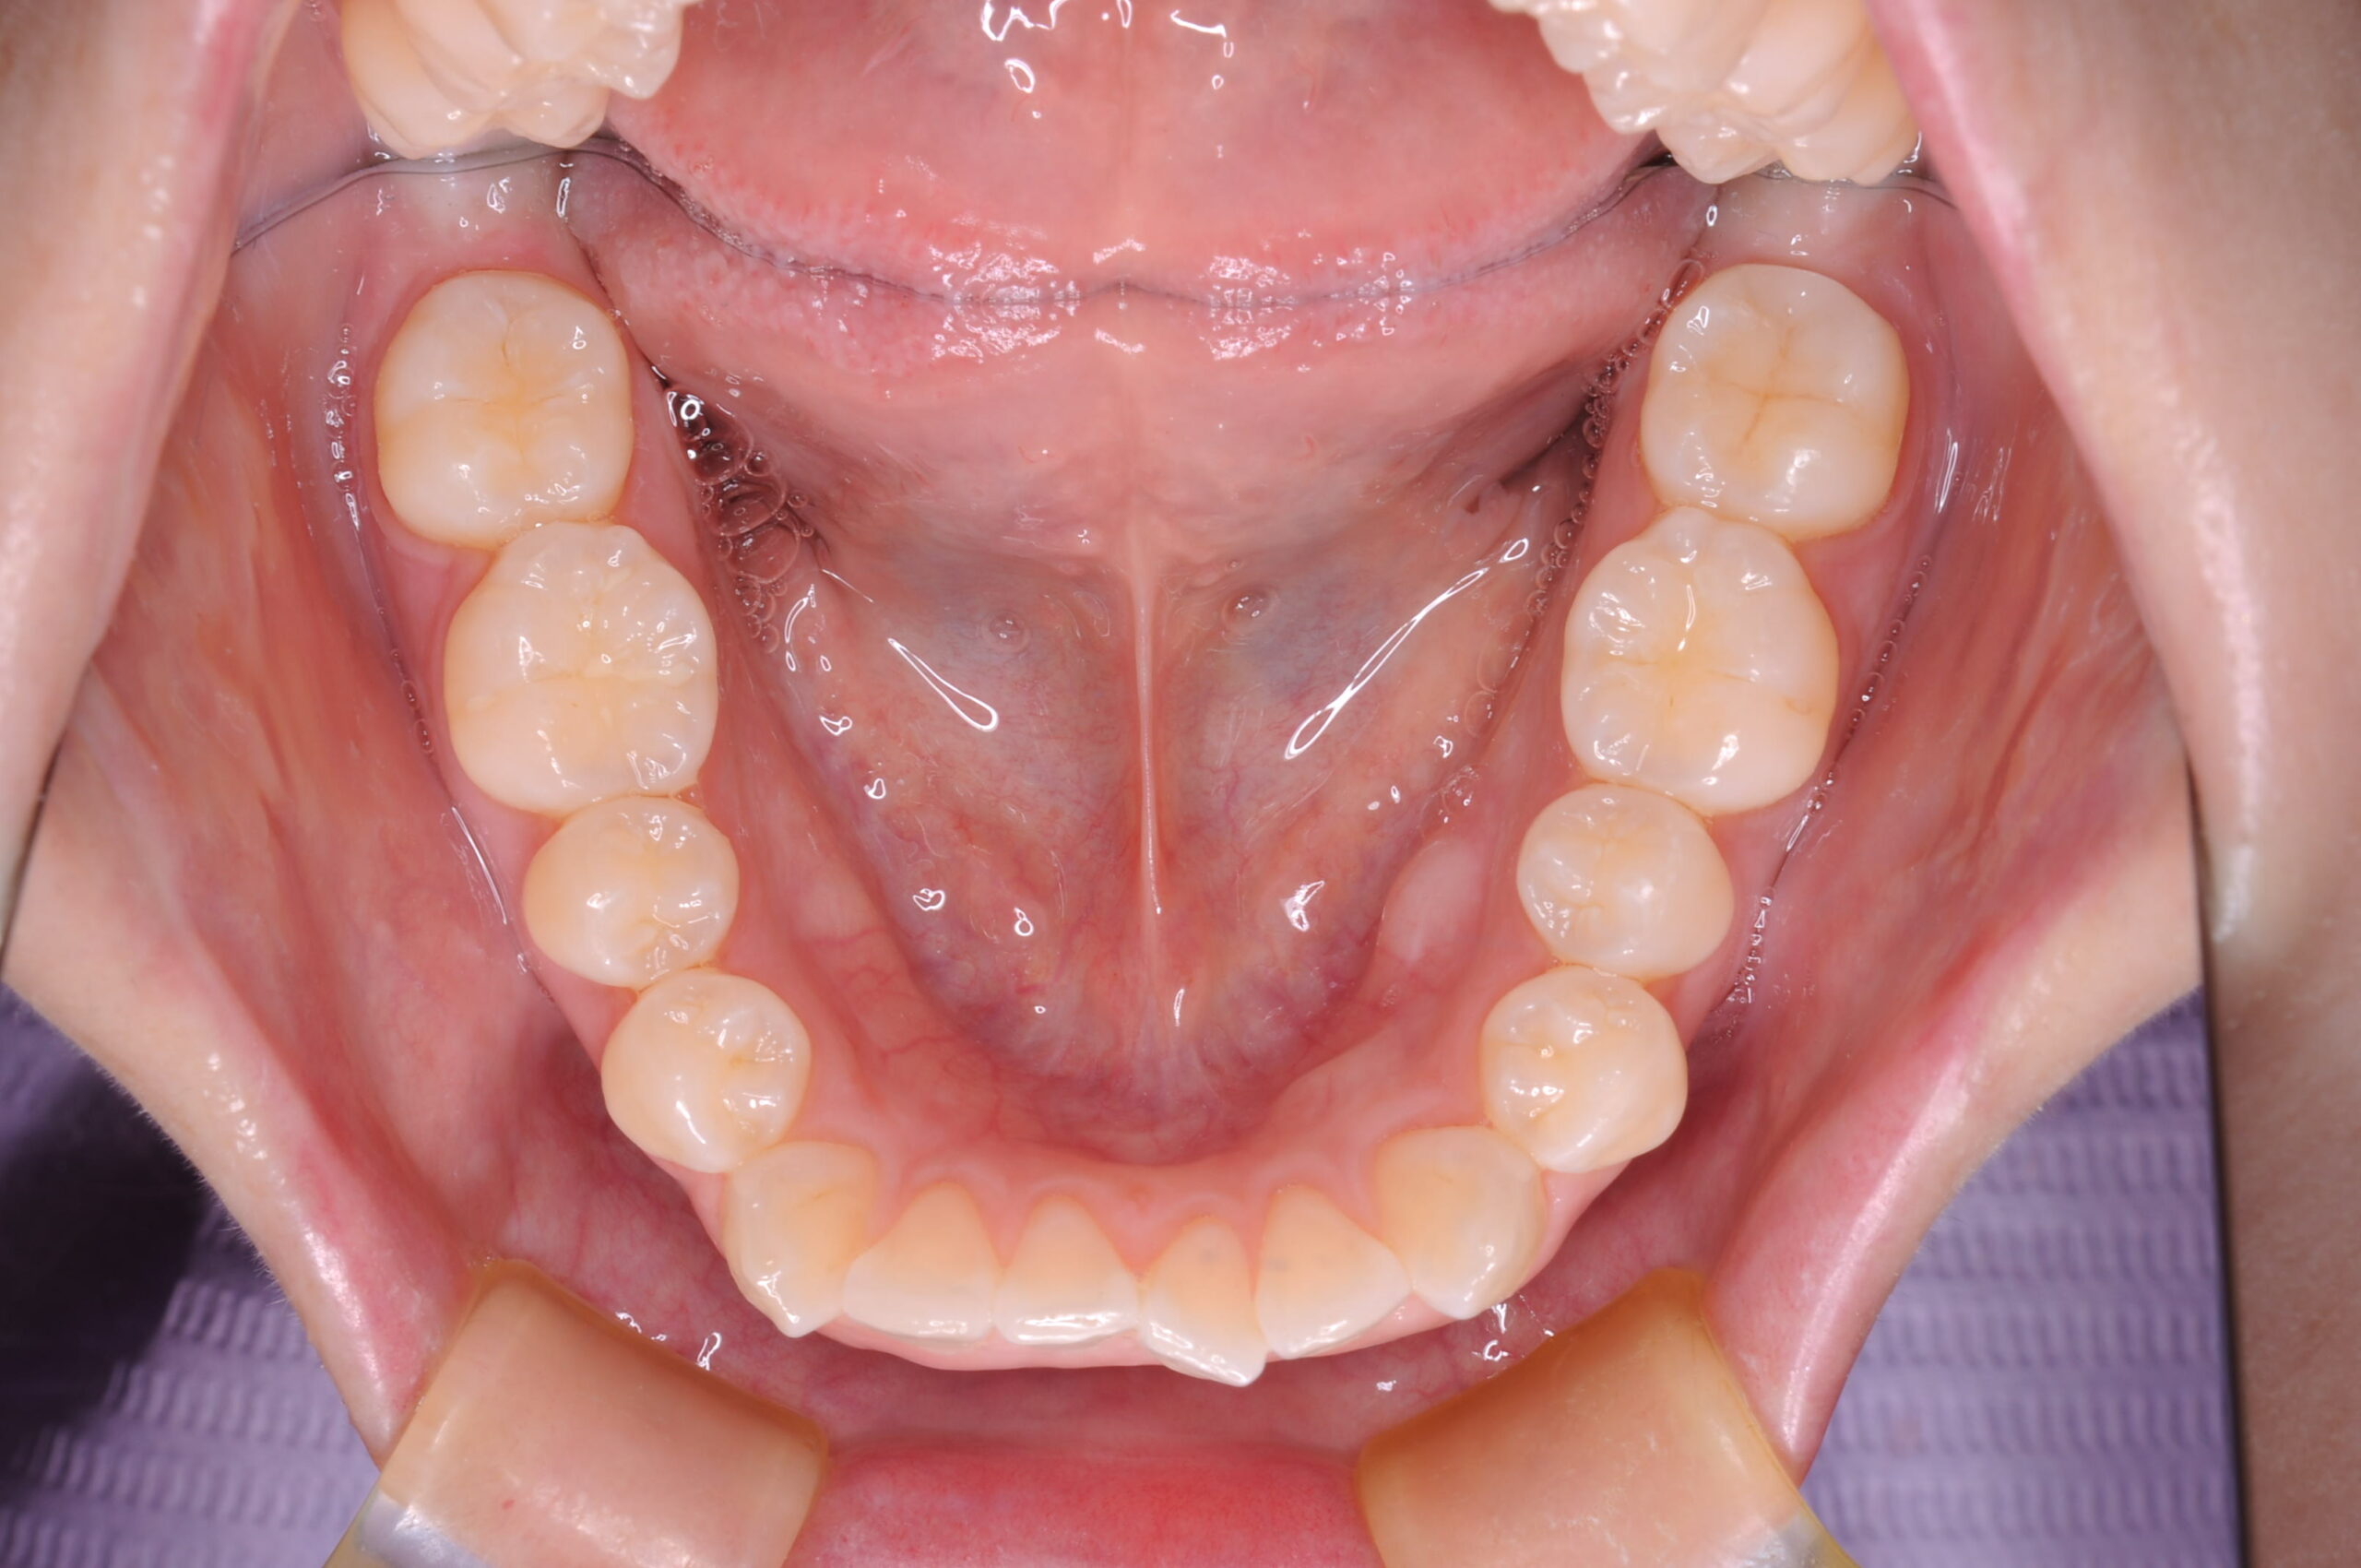

症例写真 after